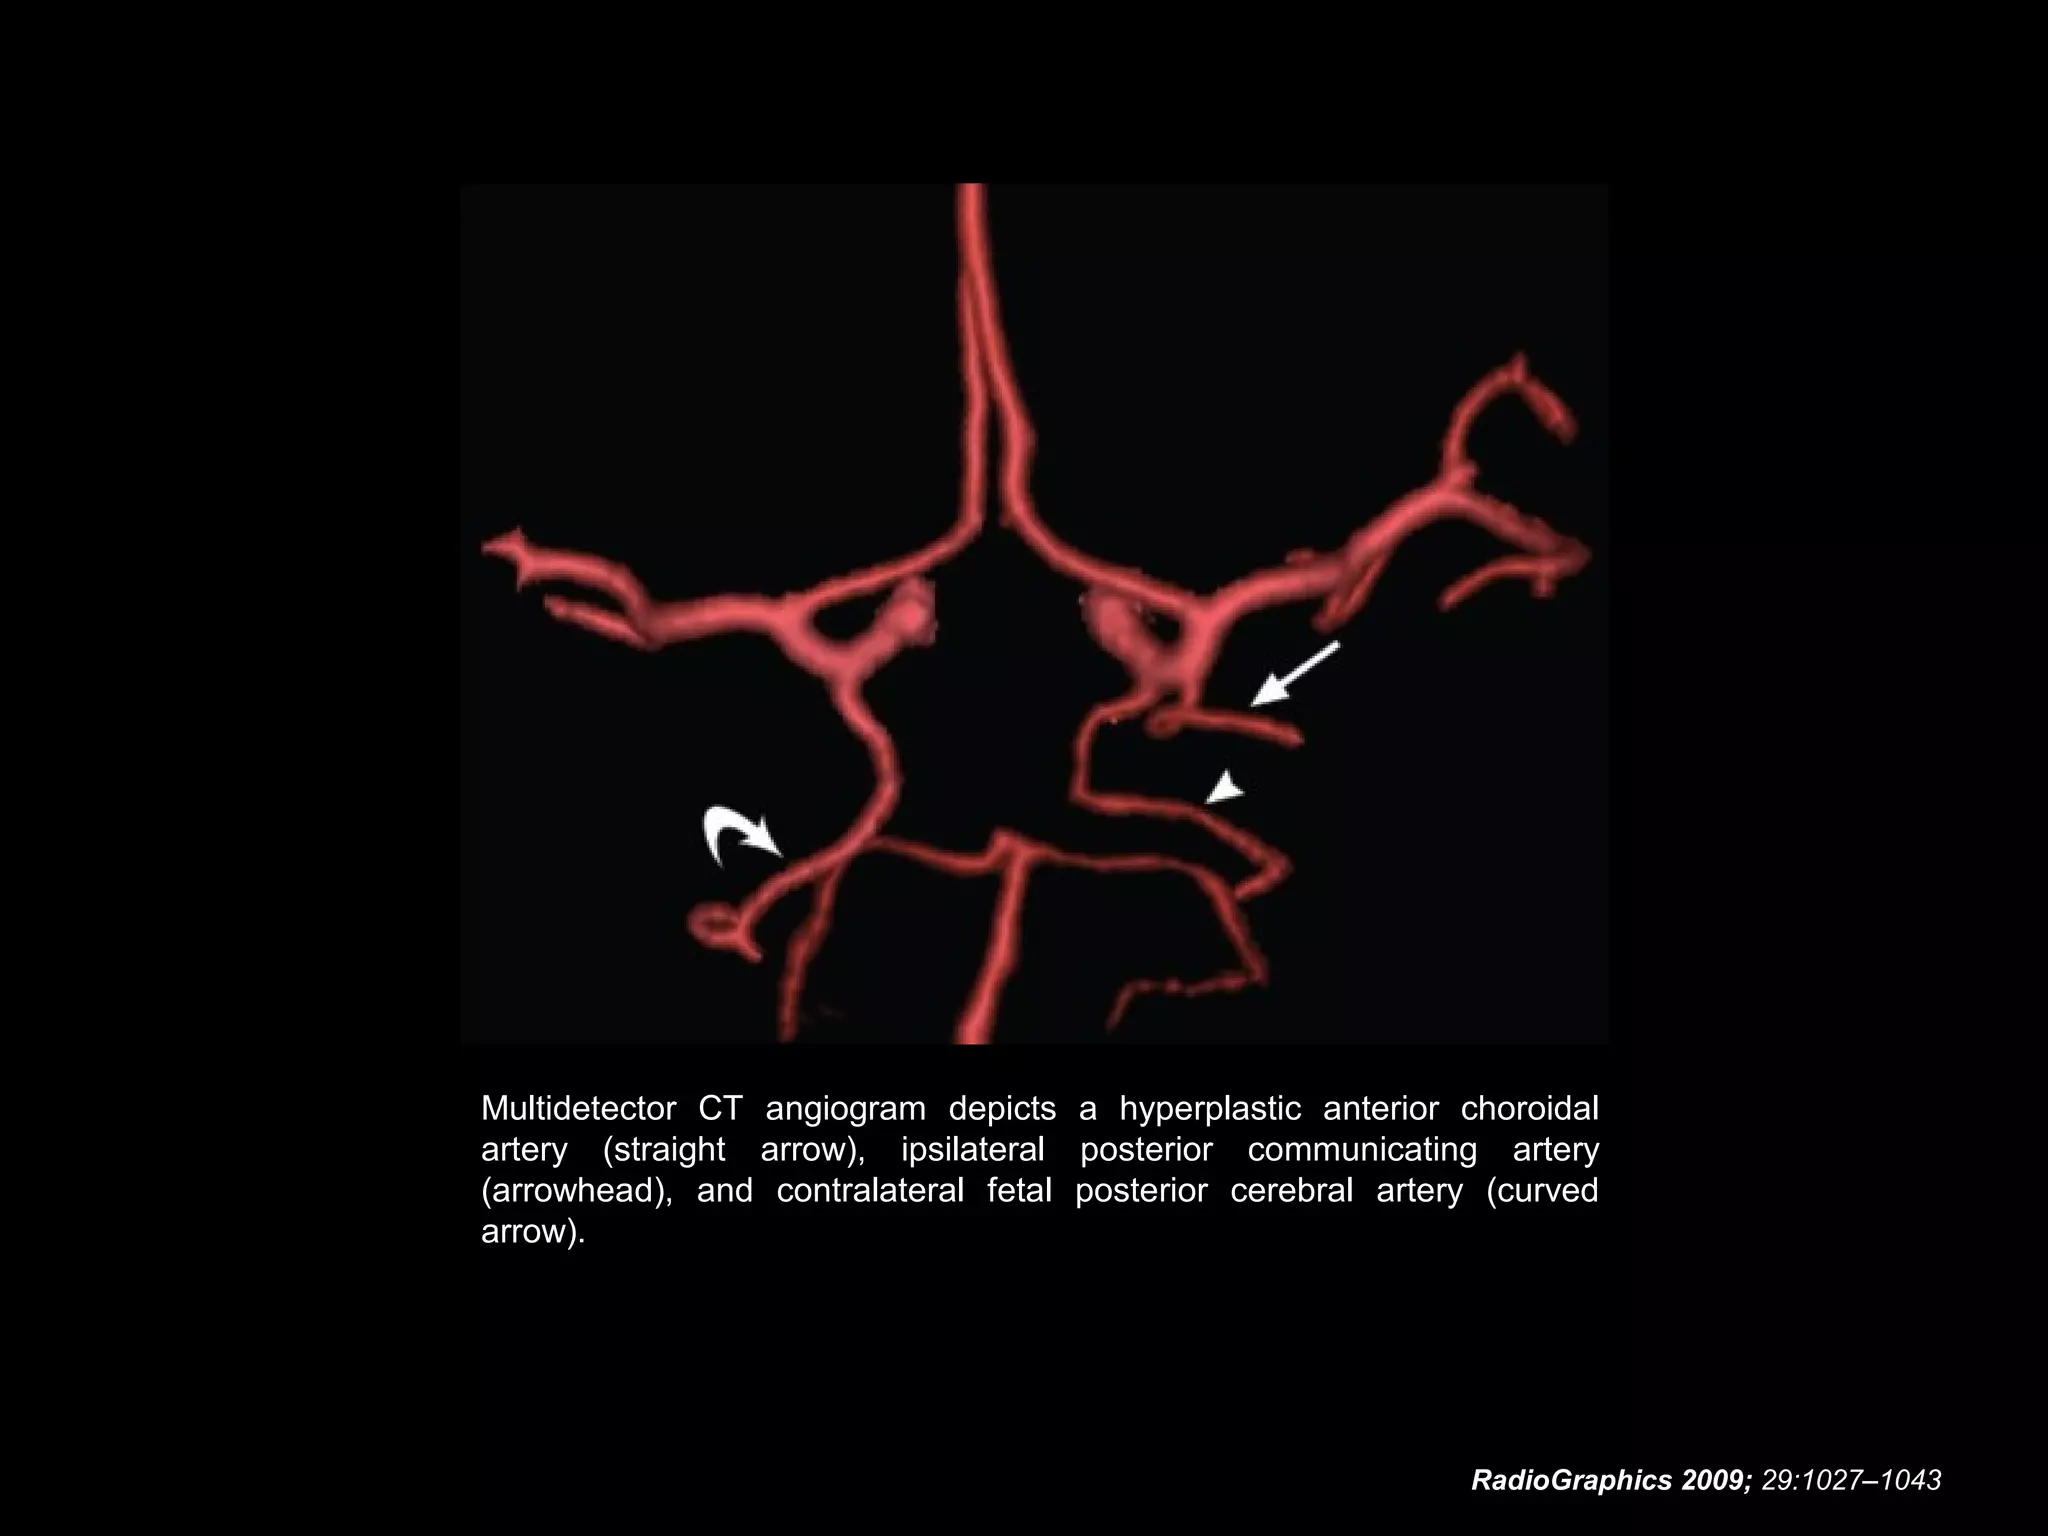

Hyperplastic Anterior

Choroidal Artery

• The anterior choroidal artery, usually a small vessel,

arises from the supraclinoid internal carotid artery just

distal to the posterior communicating artery.

• From there it subdivides into important branches that

supply the cerebral peduncle and optic tract.

• The temporo-occipital branches of the posterior cerebral

artery may arise from the anterior choroidal artery.

• In people with this cerebrovascular variant, the anterior

choroidal artery is described as hyperplastic.

• The prevalence of hyperplastic anterior choroidal arteries

is reported to be 1.1%–2.3%.

RadioGraphics 2009; 29:1027–1043

Multidetector CT angiogram depicts a hyperplastic anterior choroidal

artery (straight arrow), ipsilateral posterior communicating artery

(arrowhead), and contralateral fetal posterior cerebral artery (curved

arrow).